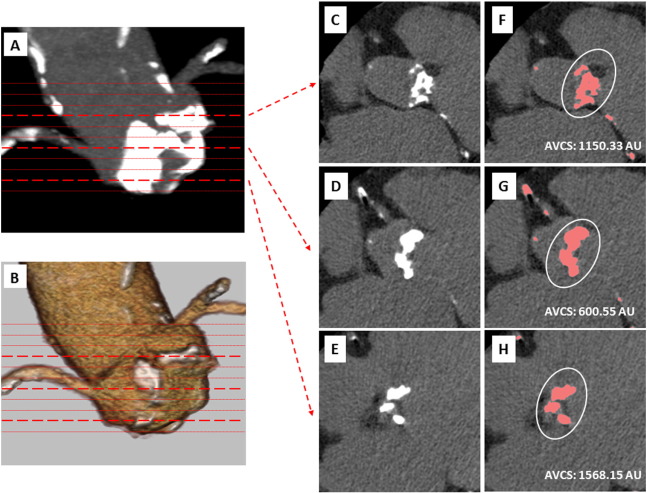

All patients were scanned using a 256-slice scanner (Brilliance iCT; Philips Medical Systems, Eindhoven, The Netherlands) at the Toyohashi Heart Center. Before MSCT angiography, a noncontrast MSCT scan was performed to measure CS according to the modified Agatston method [9] ;  [10]. Prospective electrocardiogram triggering (75% of R–R interval) was used with a slice thickness of 2.5 mm. The scan was performed between the tracheal bifurcation and the diaphragm with the following parameters: collimation width, 32 × 0.625 mm; rotation time, 330 ms; tube voltage, 120 kV; and maximum effective tube current, 64 mA. Image reconstruction was gated prospectively to 75% of R–R interval. MSCT images were reconstructed using a cardiac standard filter with a slice thickness of 2.5 mm. MSCT data sets were transferred to an offline workstation (Intelli Space Portal; Philips Medical Systems) for image analysis. MSCT data sets were transferred to an offline workstation (Aquarius NetStation; Terarecon Inc., San Mateo, CA, USA) for image analysis. AVCS and coronary calcium score (CCS) were determined 2-dimensionally by using the CS data sets on the workstation, and defined by Agatston units (AU). The AVCS area of interest comprised the sinotubular junction (STJ), valve cusp, aortic annulus, and left ventricle outflow tract; the start of acquisition was placed from the bottom of the valve to the level of the STJ. A representative example of AVCS assessment is shown in Fig. 1. CCS also was determined by summing the individual lesion scores of each of the main coronary arteries based on modified American Heart Association classification; segments with a diameter > 2.0 mm were analyzed. Luminal diameter stenosis was assessed by visual estimation, with significant stenosis defined as > 50% stenosis. Structures > 2 mm2 adjacent to the lumen that could be distinguished from the lumen and the surrounding pericardial tissue were defined as coronary plaque, as we have previously shown. All MSCT angiographic images were analyzed by 2 independent observers. In the case of different observer readings, a consensus reading was performed and used in the final analysis.

A whole image of AVCS calculation by using MSCT was presented in panels A–B. ...

A whole image of AVCS calculation by using MSCT was presented in panels A–B. Corresponding with each thin slice images, the AVCS area of interest included from STJ to aortic annulus basal plane between the red lines. Three dotted lines correlated with each section were given (panels C–E) and the AVCS calculated the other aorta or coronary calcification was excluded from the analysis (panels F–H).